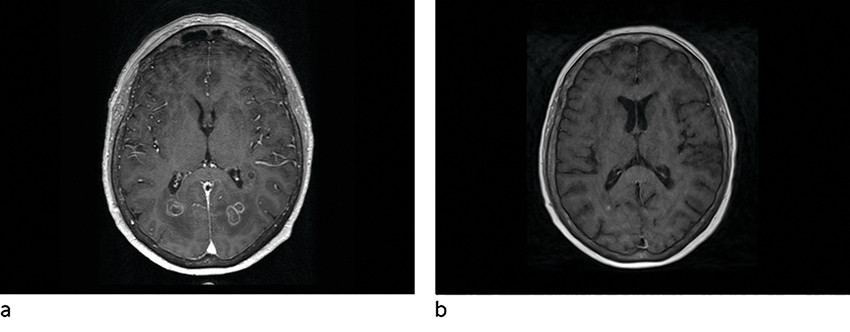

MR caput ble utført om kvelden innleggelsesdagen, ca. ti timer etter at pasienten kom på gastroenterologisk laboratorium. Denne viste multiple runde foci subkortikalt parietooksipitalt bilateralt, med moderat omkringliggende ødem (figur 1, figur 2, figur 3). Lesjonene hadde lavt T2-signal både sentralt og perifert. Det var høy diffusjon sentralt, men en tykk perifer kapsel med betydelig nedsatt diffusjon. Susceptibilitetsvektede sekvenser (SWI) viste signalbortfall både perifert og i punktformede områder sentralt, noe som kunne være blodnedbrytningsprodukter eller paramagnetiske elementer (jern, magnesium, sink, nikkel). Det var lett forhøyet T1-signal i enkelte lesjoner, hvilket også kunne tyde på innhold av blodnedbrytningsprodukter. I tillegg var det en tynn, lobulert kontrastoppladning i periferien av lesjonene, stedvis med uskarpe grenser mot omkringliggende parenkym.

Disse karakteristikaene ved lesjonene hos en immunsupprimert pasient med tegn til infeksjon gav mistanke om soppabscesser, mest sannsynlig forårsaket av Aspergillus sp.

Hjerneabscesser kan ha variable bildediagnostiske utrykk avhengig av agens og utviklingsstadier (4). Man kan ikke bestemme agens ut fra MR-undersøkelse, men karakteristika på standardsekvenser, diffusjonsvektede sekvenser (DWI) og susceptibilitetsvektede sekvenser kan brukes for å skille pyogene abscesser fra soppabscesser (4–6). Av sekvensene synes de diffusjonsvektede å være de mest sensitive for tidlig identifikasjon av cerebral aspergillose (5). Disse er også nyttige i differensieringen mellom soppabscesser og pyogene abscesser (tabell 1) (5). Begge kan vise diffusjonsrestriksjon i hulrom, men bakterielle abscesser har ofte homogen diffusjonsrestriksjon sentralt, i motsetning til soppabscesser, der signalet er inhomogent. Soppabscesser viser også typisk diffusjonsrestriksjon i veggene, noe som er uvanlig ved pyogene abscesser (5). Aspergillusabscesser er ofte multiple, med lobulerte konturer, ujevne indre grenser og variabel kontrastoppladning i periferien (4, 5). På T2-sekvenser og susceptibilitetsvektede sekvenser fremstilles lav intensitet sentralt, grunnet høy forekomst av paramagnetiske elementer (jern, magnesium, sink, nikkel), som er viktig for soppens vekst. Dette er uvanlig ved pyogene abscesser. Ved aspergillusabscesser kan man se hemoragisk nekrose (4, 5).